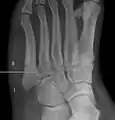

A person with a Jones fracture may not realize that a fracture has occurred. Diagnosis includes the palpation of an intact fibularis brevis tendon, and demonstration of local tenderness distal to the tuberosity of the fifth metatarsal, and localized over the shaft of the proximal metatarsal.

Diagnostic X-rays include anteroposterior, oblique, and lateral views and should be made with the foot in full flexion.